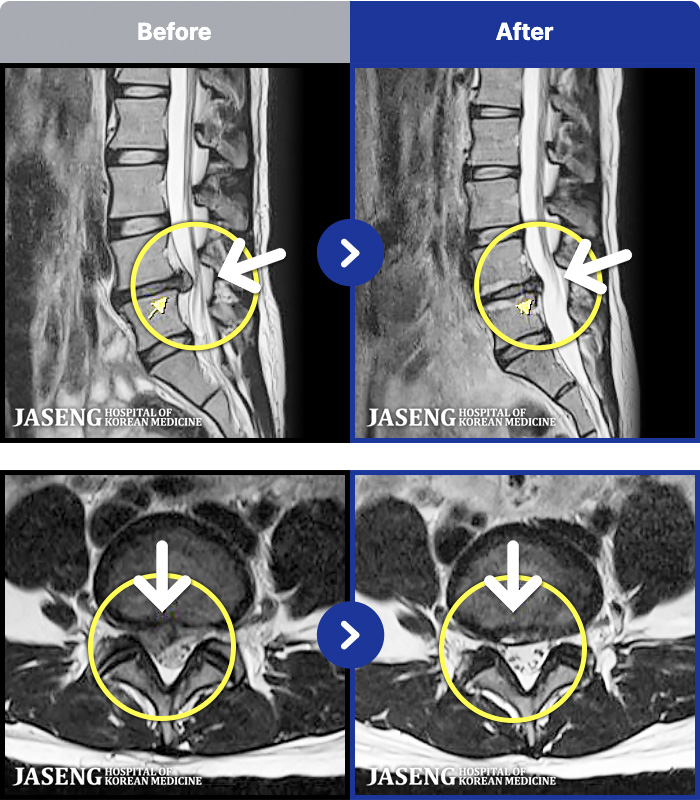

97 MRI ũ ʸ Ȯϼ.